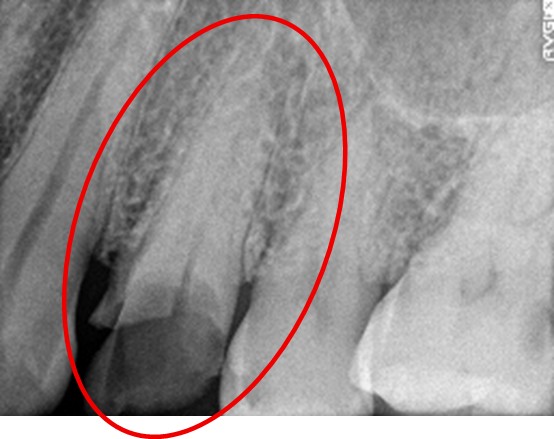

女性 Tさん 40代 (オールセラミック冠)

主訴

右上の被せものをしているところが、むし歯になり食べものがはさまるのでので、治したい。

治療内容

右下の歯が、根の先で問題を起こし、かつ歯周病でもありました。根管治療と歯周病治療をしました。

患者さんは、メタルフリーの治療を希望されましたので、ファイバーコアをいれオールセラミック冠を被せました。

所感

他院で抜歯を宣告された歯でした。根管治療と歯周病治療をすると腫れはなくなり残せると判断しました。歯のまわりの清掃の仕方をしっかり指導しました。患者さんは、丁寧に実践してくれています。

オールセラミック冠:¥86,400×1本=¥86,400